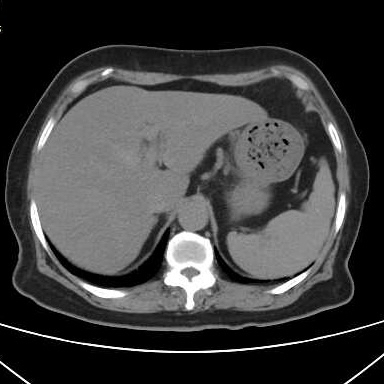

胃结石的2个病例

最近有几个吃山楂后形成胃结石的病历,第一个,老年女性,突发腹痛2天,持续性钝痛,阵发性加重,伴恶心,呕吐胃内容物,性状无异常,呕吐后无缓解,入院后抑酸治疗效果不理想,CT如下图。考虑...